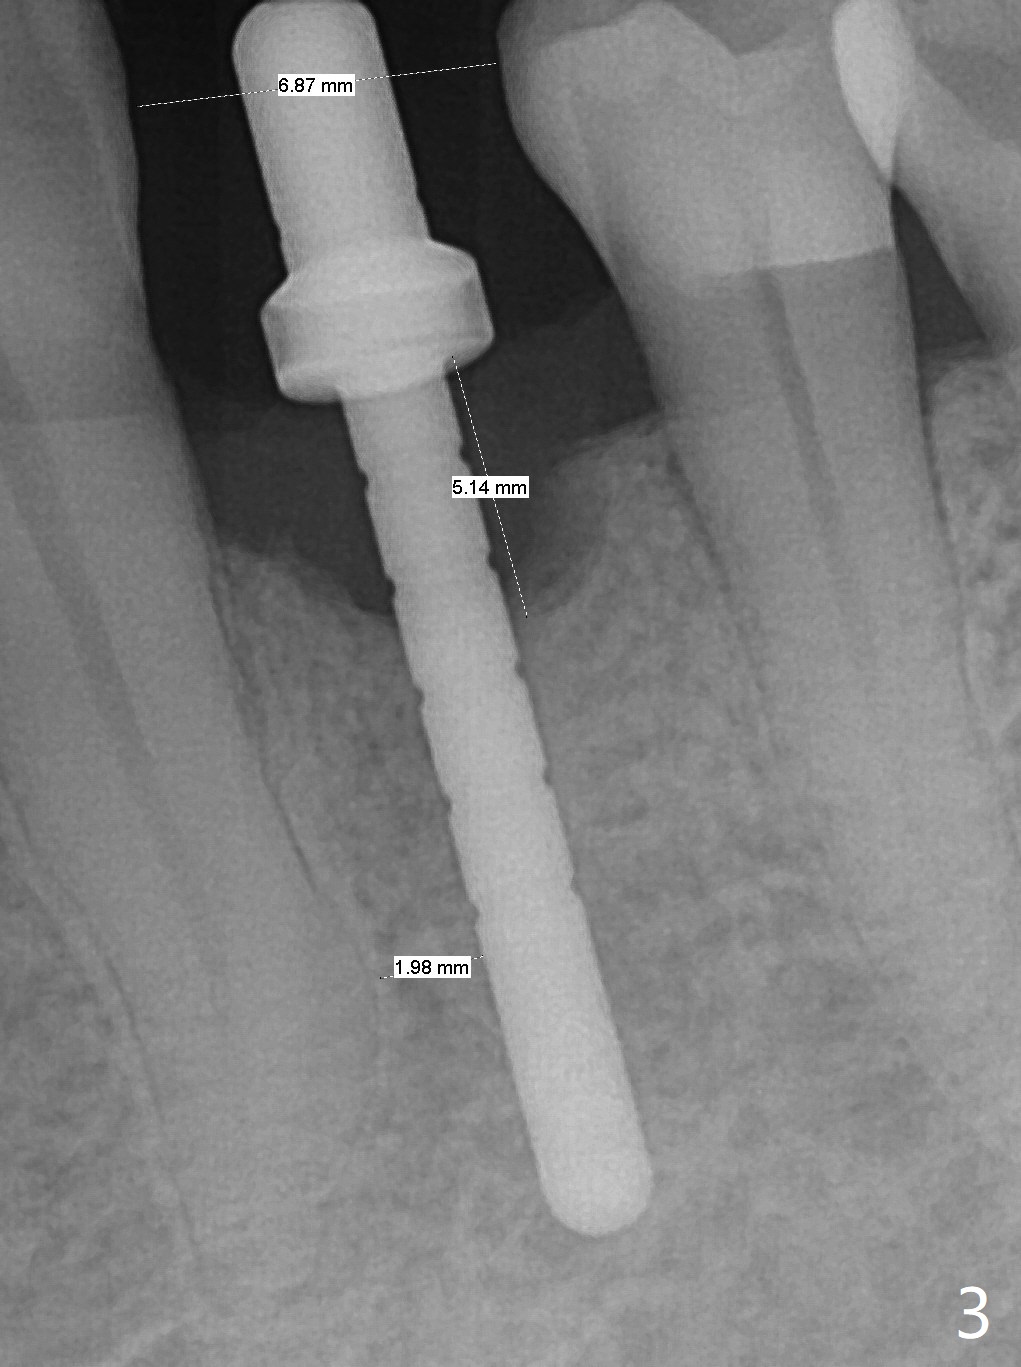

After incision at #21 (Fig.1) and flap elevation, the narrow ridge is reduced and initial osteotomy is made (Fig.2,3). Following moving the osteotomy distal, a 3x12(4) mm 1-piece implant is placed with >35 Ncm (Fig.4-6). Vanilla Graft is placed in the most concave buccal defect (Fig.1,4 *) and over the ridge reduction area (Fig.6 *). No bone loss is observed 3 months postop (Fig.7).